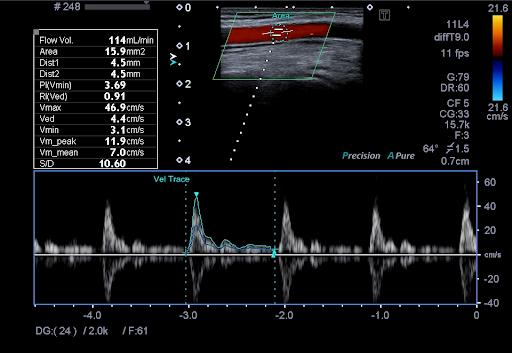

ADF - Advanced Dynamic Flow™* позволяет визуализировать мельчайшие кровеносные сосуды и регистрировать кровоток с непревзойденной точностью и детализацией.

Auto-IMT - это удобный и простой в использовании инструмент для автоматизации измерения толщины интима-медиа (IMT) проксимальных и дистальных стенок артерий. Данная технология незаменима для определения риска сердечно-сосудистых заболеваний у пациента.